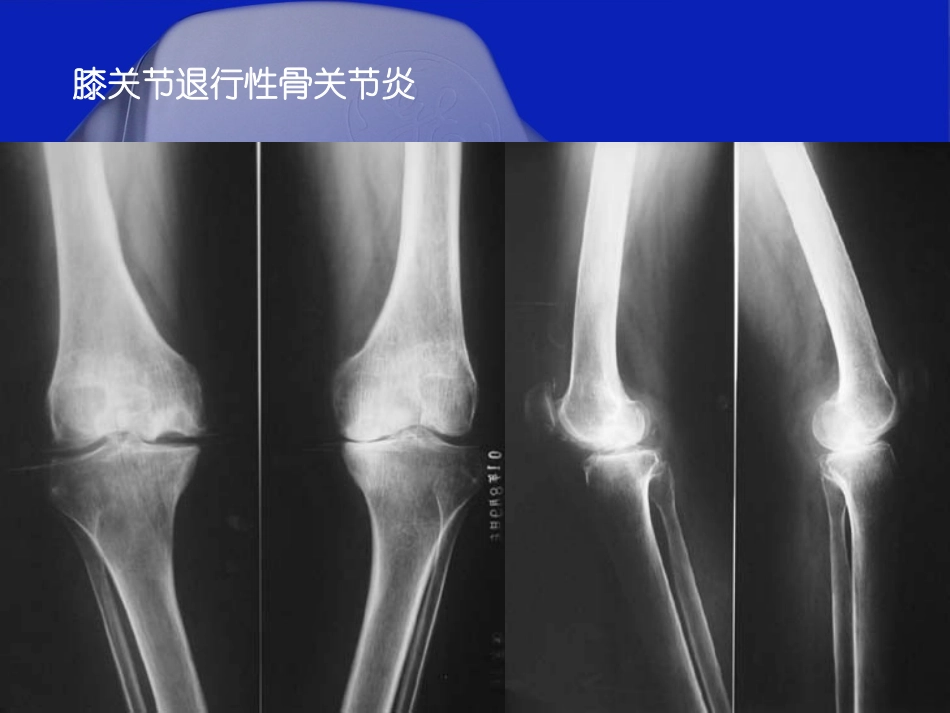

四川省名中医学术继承人四川省名中医学术继承人成都骨科医院成都骨科医院潘良春副主任医师潘良春副主任医师2011QQ15252811健康教育中心群:92定义骨关节炎(OA)是一种退行性疾病,一般认为与衰老、创伤、炎症、肥胖、代谢障碍、遗传等因素有关,其发病机制尚不十分清楚。2011QQ15252811健康教育中心群:93膝关节退行性骨关节炎2011QQ15252811健康教育中心群:94流行病学本病的患病率随着年龄增加而升高。70岁以下膝关节患病率为7%,80岁以上为11.2%。放射学所见膝关节骨性炎症改变,70岁以下为27.4%,80岁以上为43.7%。2011QQ15252811健康教育中心群:95流行病学国内的一组统计无症状骨性关节病的发病率为53%。30-39岁11%40-49岁27%50-59岁62%2011QQ15252811健康教育中心群:96发病关节颈椎、腰椎、膝、髋、手指、足部较多男女性别在脊椎关节病上的差异不大,但膝、髋等部位发病以女性较多,国内的几组统计,男女比例约为1:1.5。2011QQ15252811健康教育中心群:97临床表现疼痛为本病常见症状,早期疼痛较轻,休息后可缓解。随着病情进展疼痛加重,可有夜间疼痛发生。另一主要症状为活动受限,呈缓慢的交替性进展。随病情的发展,症状可逐渐加重。2011QQ15252811健康教育中心群:98**膝关节骨关节炎症状膝关节骨关节炎症状膝关节骨关节炎可为单发性,亦可以是双侧性,仍以女性女性偏多见,往往体重超标体重超标。在进入中年中年后出现症状,当从坐位起立行走时觉得膝部酸痛不适,走了一段时间后症状消失,这是早期膝关节骨关节炎的临床表现。随着疾病的进展,发现活动并不能缓解疼痛,并出现上下楼梯,下蹲与从座位上站起来都有些困难,需要用手在膝盖上撑一下才行。多走路后膝关节还有些肿肿,部分病例膝部肿得厉害,还可以抽出一些淡黄色液体。由于滑膜与关节囊有病变而增厚,活动时可有响声响声,如果是关节内有游离体形成,可影响关节活动,并不时有“关节绞锁”现象。到最后出现膝关节畸形,例如膝关节屈曲挛缩,O形腿或X形腿,甚至拄拐杖才能行走。2011QQ15252811健康教育中心群:99病因年龄因素:随年龄增加,组织、细胞的退变。外伤、运动过度。职业和关节的过度使用。肥胖:增加关节负重及引起不当姿势和步态。遗传和某些先天性疾病。2011QQ15252811健康教育中心群:910与骨质疏松相关性?2011QQ15252811健康教育中心群:911病理滑膜的各种炎性反应、增生和表面渗出。关节囊的增厚和粘连。关节软骨的软化、撕裂、磨损。骨赘形成。2011QQ15252811健康教育中心群:912正常软骨软骨局部变软、糜烂、变薄脱落边缘出现骨刺不断流失继续流失骨关节炎的形成痛在关节,病在软骨!2011QQ15252811健康教育中心群:913骨关节炎的疼痛–摘自《骨关节炎十年》痛在关节,病在软骨!骨关节炎(Osteoarthritis,OA)退行性骨关节病,退行性关节炎,骨关节病OA是在力学因素和生物学因素的双重作用下软骨细胞、细胞外基质及软骨下骨三者之间分解合成代谢失衡的结果2011QQ15252811健康教育中心群:914骨关节炎的表现主要表现为滑膜增厚、关节积液、半月板损伤、软骨的损伤和骨的赘生等。滑膜增厚在轻度的骨关节病中表现常不明显。2011QQ15252811健康教育中心群:915关节软骨的改变软骨水肿、软骨囊性变、软骨变薄和不同程度的磨损、软骨破坏等。2011QQ15252811健康教育中心群:916小囊状缺损层次模糊消失表面毛糙局部全层缺失弥漫性变薄2011QQ15252811健康教育中心群:917骨赘(骨质增生)的形成大多发生于关节软骨边缘处,沿应力线方向排列。骨赘可突入关节腔,位于关节囊和韧带附着处。骨赘可呈环状,形成骨桥。关节内游离体。2011QQ15252811健康教育中心群:918关节纤维性强直关节骨性强直2011QQ15252811健康教育中心群:919骨赘形成,髋关节活动受限。2011QQ15252811健康教育中心群:920骨关节炎的危害骨关节炎发病率较高据WHO统计,50岁以上的人群中,发病率为50%,60岁以上的人群为80%我国的流行病学调查显示,人群患病率为9.6%;65岁以上人群中90%的女性和80%的男性患有关节炎中国有1亿人患有骨关节炎骨关节炎严重影响患者的健康及行动能力2011QQ15252811健康教育中心群:921O...